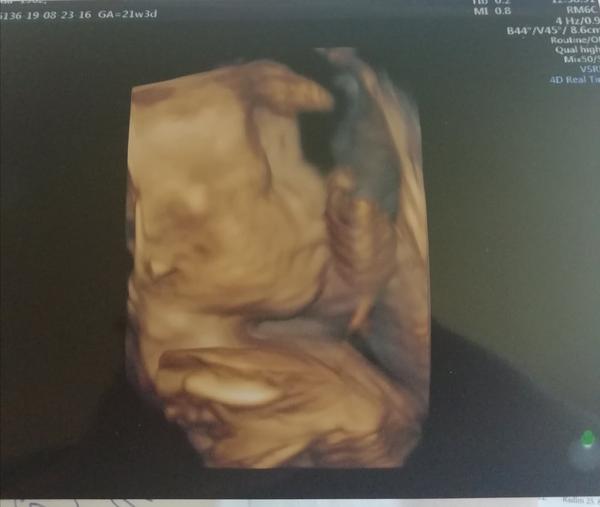

Ahoj holky, tak my máme 2. screening za sebou, byli jsme včera. Vše je v naprostém pořádku a na svém místě, vše funguje tak, jak má, opět potvrzena holčička a bylo super ji opět vidět 🙂 Pán doktor ultrazvuk přepnul na chvíli i na 3D a je to mazec vidět už ty rysy obličejíčku 🙂 Jinak my chodíme do Brna do Prenatalu, platili jsme 1200 Kč a dostali jsme 3D fotečku a nahrávku celého ultrazvuku na CD. Tak pak pisnite váš zážitek 😇

Ahojky holky, tak u nás na druhem screeningu vsechno na jednicku🙂 Mame na 100% pindu pry🙂 tak uz tomu zacinam verit teda🙂 akorat byl celou dobu v poloze sklapovacka, nohy i ruce pred oblicejem, takze rysy smolik a jsme preobjednani na ten 25tt, tak doufam, ze to bude spolupracovat🙂 🙂

@laloogrey @jennas Ahoj holky, tak to oběma gratuluju k pozitivním zprávám, to je moc dobře! 😍 Jsem ráda, že se nám daří, ale zároveń to klepu!!🙂 Já byla v pondělí na kontrole a včera na 3D utz. Na kontrole ok, jsem ve 22+1 a nahoře mám cca 4,2 kg, tak snad je to ok. Nikdo k tormu nic neříkal A vyfasovala jsem žádanku na cukrovku, tak za 14 dní se mám objednat. Tobě @laloogrey držím palce, aby pro tebe ta zvýšená hodnota nic neznamenala a bylo všechno ok!! 😉Jinak já vám taky ukážu naši malou princeznu na fotečce, co jsme dostali🥰